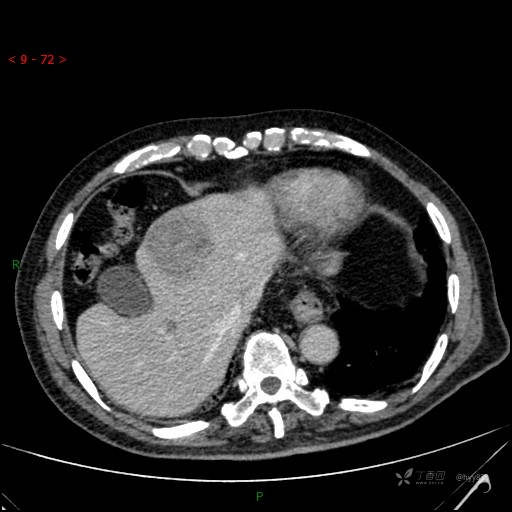

延迟期

img

肝脓肿 (73)